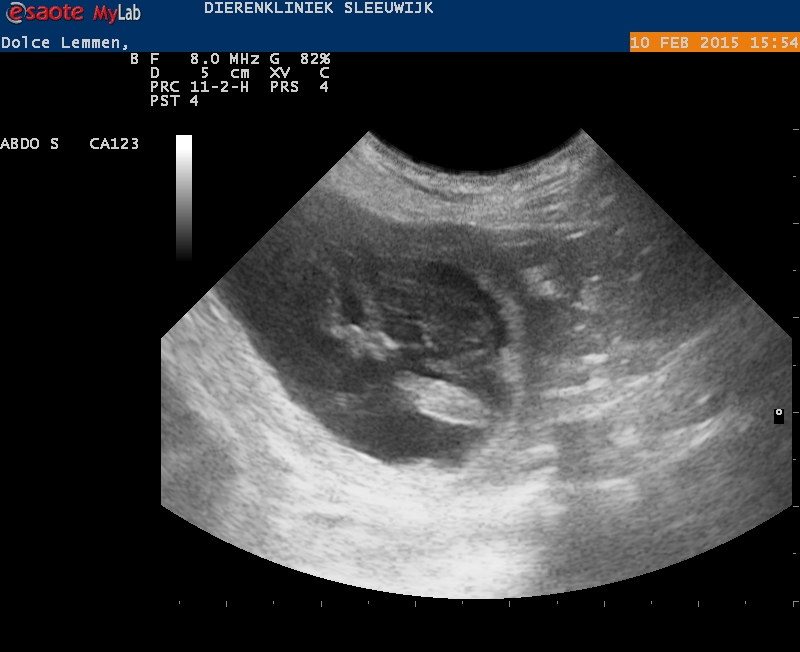

Vandaag hebben we het bevestigd gekregen, wat we eigenlijk al wisten: Dolce is zeker weten drachtig!

Tijdens de echo hebben we de vruchtjes kunnen zien, de hartjes zien kloppen en de dierenarts vond dat ze goed ontwikkeld waren.

We doen de echo eigenlijk vooral ‘voor de lol’, maar het blijft altijd prachtig om te zien! Dolce is zoals altijd heel relaxed dus ook dit liet ze kalm over zich heen komen, ze stond zelf ook heel geïnteresseerd naar het schermpje te kijken.